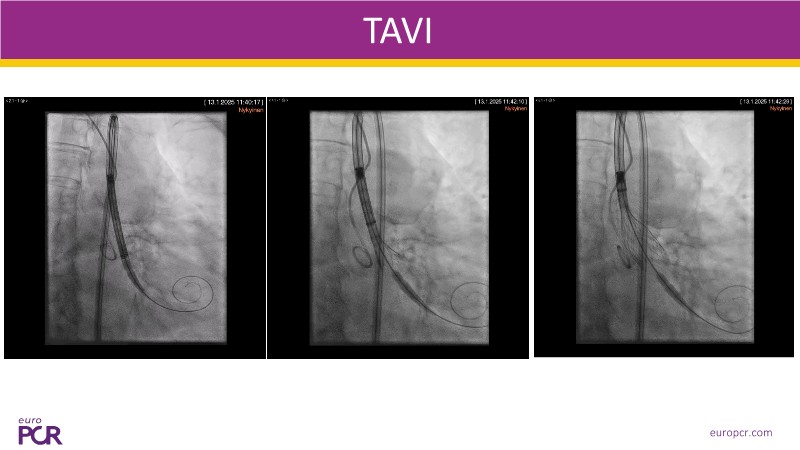

This session explores some of the most clinically complex scenarios encountered in TAVI practice. Three real-world cases address key challenges such as intervention sequencing and transcatheter valve selection in patients with combined coronary artery disease and severe aortic stenosis. The session also examines coronary obstruction risk assessment and protection strategies during redo TAVI, and discusses specific implantation techniques for anatomically complex cases, including large aortic valve anatomy.

- To learn how to tailor your TAVI technique to complex clinical scenarios